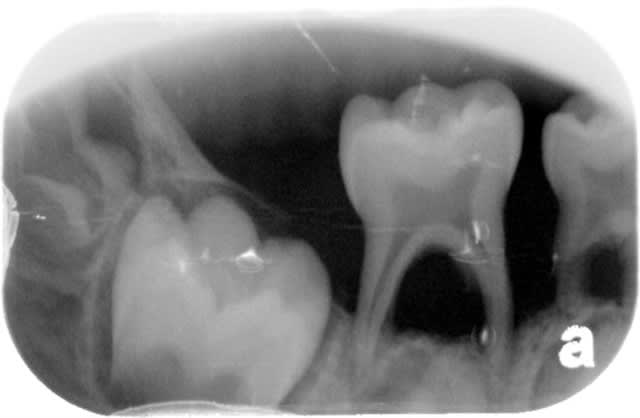

Sans compter que si on se lasse de la paro de l'adulte, on peut toujours passer à la paro de l'enfant :

Paro p do 1 fvzzcp - Eugenol

Paro p do 2 udoc3y - Eugenol